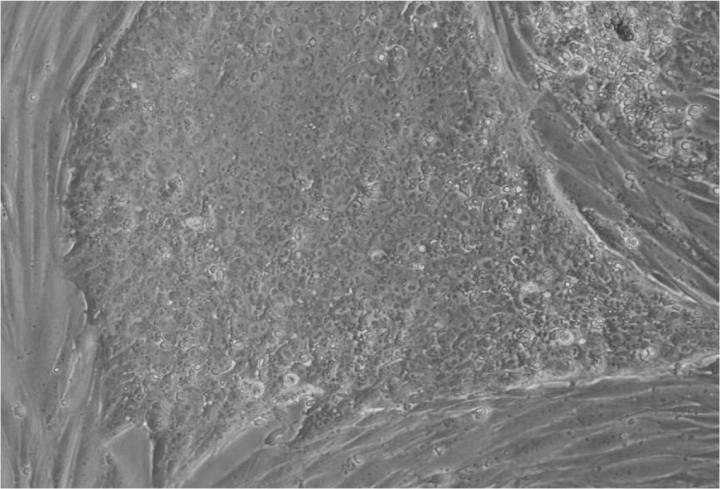

人類(lèi)胚胎干細胞 (ESC) 是從囊胚(一種非常早期的人類(lèi)胚胎)中發(fā)現的少量細胞產(chǎn)生的。從囊胚中取出的單個(gè)細胞生長(cháng)成大量細胞以產(chǎn)生 ESC“系”。

胚胎干細胞的自我復制能力允許從干細胞系中培養出大量細胞,并與全球實(shí)驗室共享多年,從而最大限度地減少了從囊胚制造新胚胎干細胞的需求。

胚胎干細胞研究的重點(diǎn)是干細胞系。這些是細胞群,都攜帶相同的基因,在實(shí)驗室中通過(guò)許多代細胞的許多生長(cháng)和分裂周期生長(cháng)。一個(gè)細胞系可以為許多研究人員提供大量細胞。

Jenny Nichols 拍攝的人類(lèi)囊胚和人類(lèi)胚胎干細胞圖像。愛(ài)丁堡大學(xué) MRC 再生醫學(xué)中心向 SCNT 和多莉羊注射細胞核。